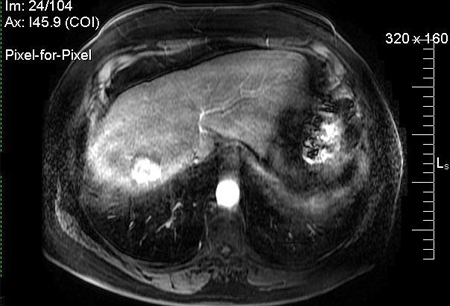

MRI: hypervascularity on the arterial phase

From the personal collection of Badar Muneer MD, Florida Hospital Transplant Center, Orlando, FL; used with permission